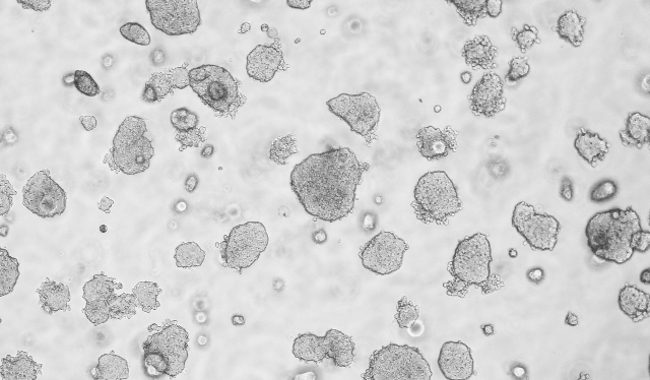

平板克隆形成圖像分析

平板克隆試驗是一種常用的測量細(xì)胞生長能力的技術(shù),從開始已知的細(xì)胞群體監(jiān)測菌落的形成。菌落的形成需要密集的分裂的原始細(xì)胞,所以在整個實驗的細(xì)胞或菌落的數(shù)量的量化是細(xì)胞的生長潛力的指標(biāo)。因此,集落形成試驗已成為一種廣泛用于癌癥研究的方法來研究藥物和電離輻射療法對癌細(xì)胞增殖的影響。